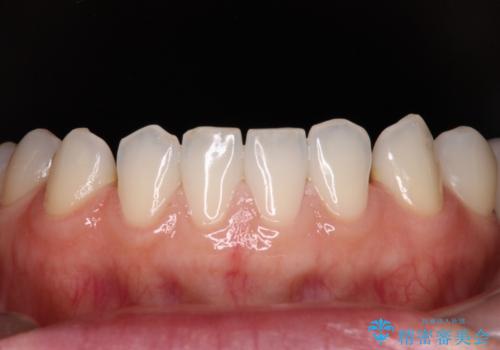

- 大きすぎる上顎前歯と、隙間の空いた下顎歯列を気にして来院された患者様です。

下顎前歯は空隙歯列弓であったので、アンカースクリューとワイヤー装置を用いてスペースを閉じていくこととし、上顎前歯は矯正治療用の仮歯に置き換えた上で、仮歯の大きさを削って小さくしながら、上下前歯部の部分矯正を行うこととしました。

日本と海外を拠点に仕事をされていらっしゃるため、数ヶ月治療があいてしまうことがあり、期間はかかりましたが、2年間で望み通りの前歯に仕上げることができました。